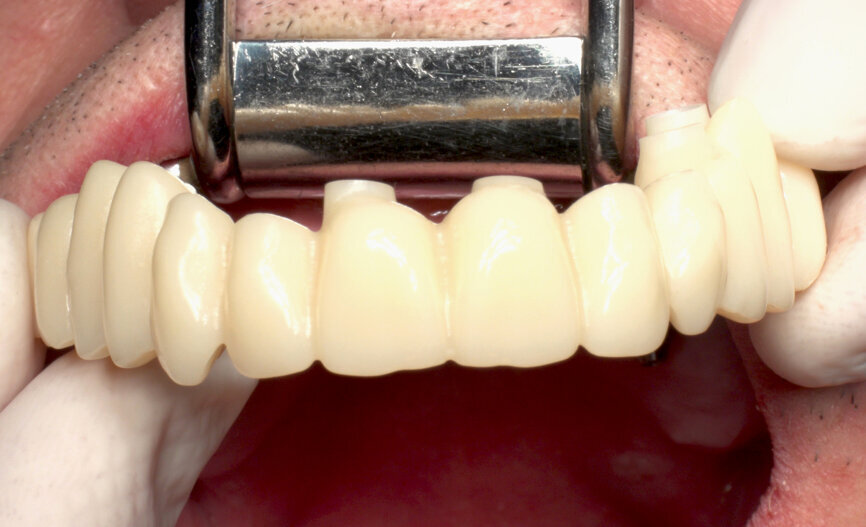

Finally, the designed temporary was sent to the milling unit and produced on a convenient PMMA disc (Telio CAD, Ivoclar Vivadent), resulting in a perfect full-arch bridge about 2 hours later. In this case, using SRAs, a monolithic Telio CAD bridge was produced without any Variobases (Straumann) for the SRAs. Final temporary production steps included characterisation and polishing (Fig. 18).

Returning to the patient, the healing caps were removed (Fig. 19), and the prosthesis was placed, allowing for a passive fit on the abutments, with an initial handpiece tightening of each SRA screw to 5 N cm. After the seating was checked, the torque of each SRA screw was increased, also with the handpiece, to 35 N cm (Fig. 20). The occlusion was checked and contacts were inspected (Fig. 21). The screw holes were sealed with PTFE and a temporary filling material. A panoramic X-ray was taken, and SRA screw positions were evaluated to confirm the perfect temporary bridge fit (Fig. 22). The patient was discharged on 500 mg of amoxicillin every 8 hours and 25 mg of dexketoprofen every 12 hours for one week. Oral hygiene and diet instructions were given, and a one-week follow-up appointment was scheduled.